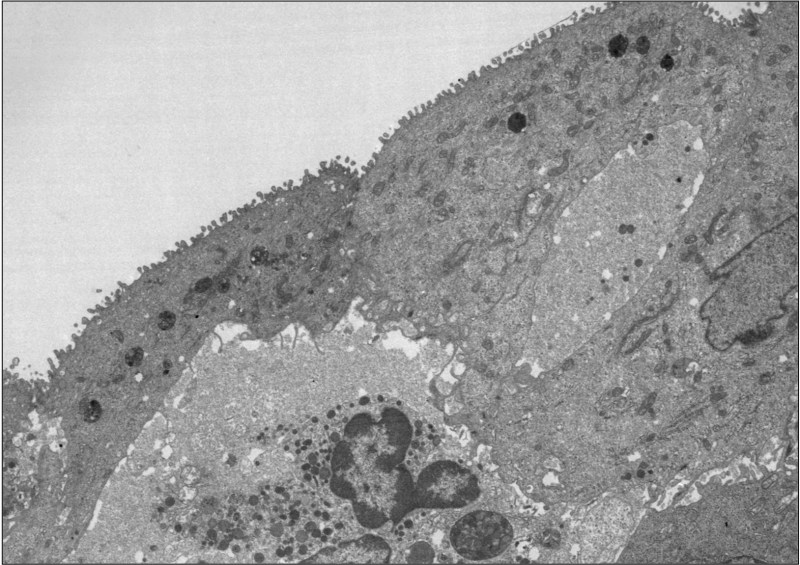

Electron Microscopy

- Cilial ultrastructures are only evaluated on good cross-sections of mid-shaft cilia.

Ultrastructure of Normal Cilia

- Specificity is high

- Sensitivity is low; approximately 20% of PCD shows normal EM

- Should not rely on as a single diagnostic test

- Microtubular doublets “9+2” configuration

- A central pair

- 9 doublets in an outer circle

- Outer doublets have:

- Inner dynein arms (IDA)

- Attached at repeated 96 nm interval

- Outer dynein arms (ODA)

- Attached at repeated 24 nm interval

- ODAs more frequently appear on cross-sections than IDA.

- Nexin

- Radial spokes

- Central sheath